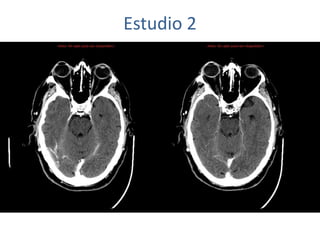

Estudio 2

• Estudio sin y con contraste, con reconstrucciones sagitales y coronales

del estudio con contraste.

Se observa una lesión ocupante de espacio en lóbulo frontal derecho que

presenta un tamaño de 18 x 32 x 22 mm (cc x ap x tr), bilobulada, no del

todo bien delimitada, con realce en anillo irregular, con hipocaptación

central, probablemente por necrosis, y asociada a un extenso edema

vasogénico con efecto masa tanto sobre los surcos de la convexidad

como sobre la cisterna insular, el sistema ventricular y la línea media,

esta última con un desplazamiento de 5 mm a la altura del septo

interventricular.

No se aprecian otras lesiones focales intra o extraaxiales de significación

patológica.

Habría que considerar como primera posibilidad que se tratase de una

lesión metastásica, por bien un tumor primario, aunque no se puede

descartar otras opciones, sin imprescindible correlación con la clínica y

con sus antecedentes.